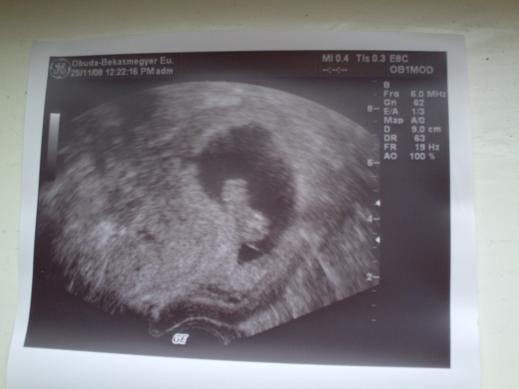

Nem elég, hogy be vagyok parázva a barnázás miatt, a doki csak nagy nehezen találta meg a kis nokedlimet!

Mondta is, hogy jól elbújt.